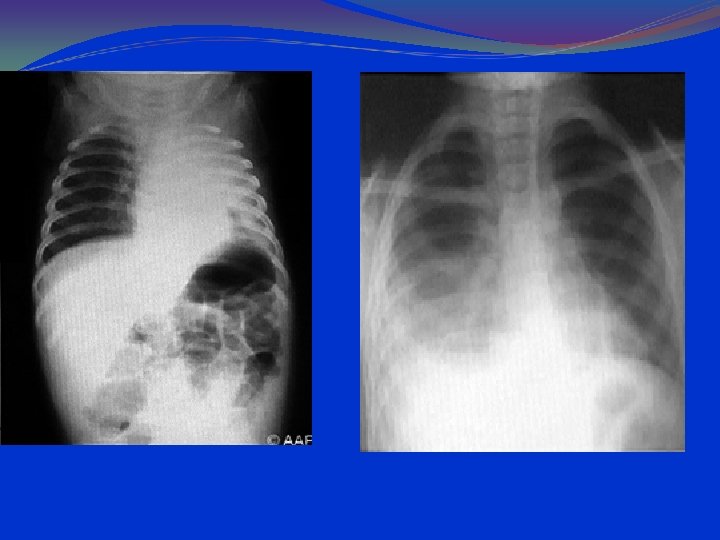

Anteroposterior radiograph of a child with a bacterial pneumonia

parahilar peribronchial infiltrates hilar adenopathy